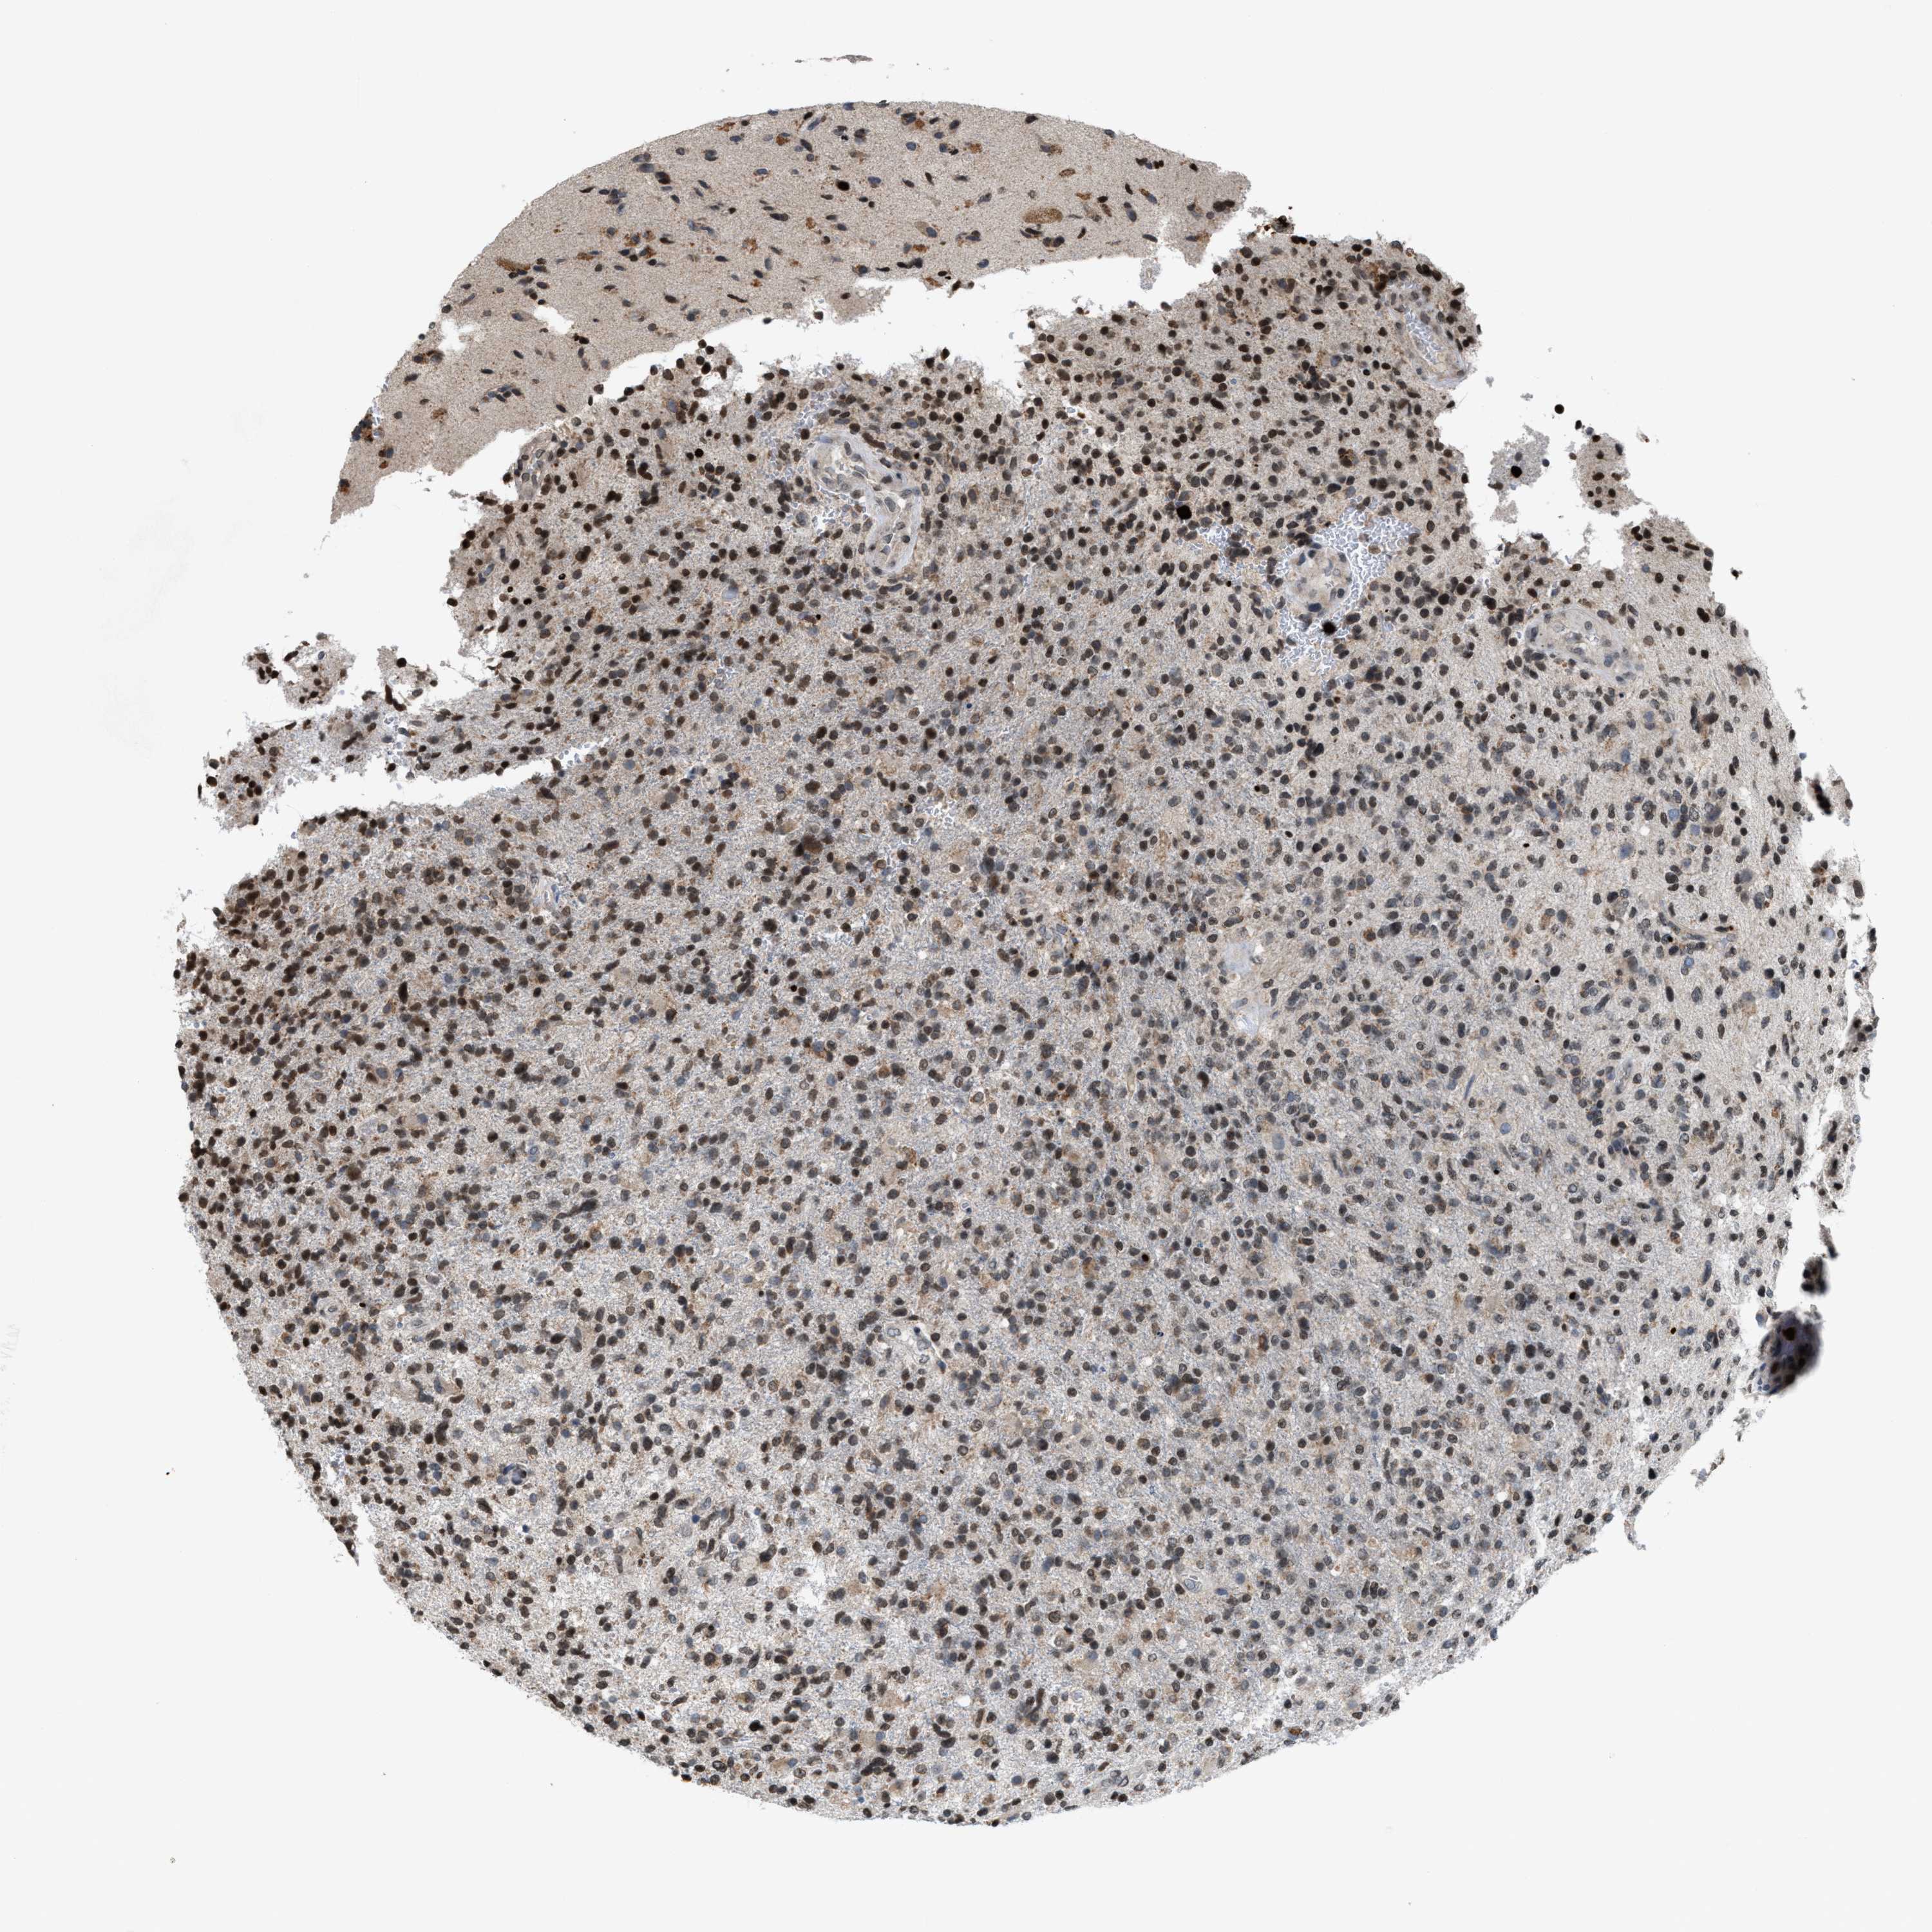

GLIOMA - Protein expressioni

A mouse-over function shows sample information and annotation data. Click on an image to view it in a full screen mode. Samples can be filtered based on level of antibody staining by selecting one or several of the following categories: high, medium, low and not detected. The assay and annotation is described here.

Note that samples used for immunohistochemistry by the Human Protein Atlas do not correspond to samples in the TCGA dataset.

Antibody stainingi

Antibody staining in the annotated cell types in the current human tissue is reported as not detected, low, medium, or high, based on conventional immunohistochemistry profiling in selected tissues. This score is based on the combination of the staining intensity and fraction of stained cells.

Each image is clickable and will lead to virtual microscopy that enables deeper exploration of all samples and also displays staining intensity scores, fraction scores and subcellular localization as well as patient and tissue information for each sample.

Antibody HPA022470

Antibody HPA031079

Staining

High

Medium

Low

Not detected

Intensity

Strong

Moderate

Weak

Negative

Quantity

>75%

75%-25%

<25%

None

Location

Nuclear

Cytoplasmic/membranous

Cytoplasmic/membranous,nuclear

Glioma, malignant, High grade

Glioma, malignant, Low grade

Glioblastoma, NOS